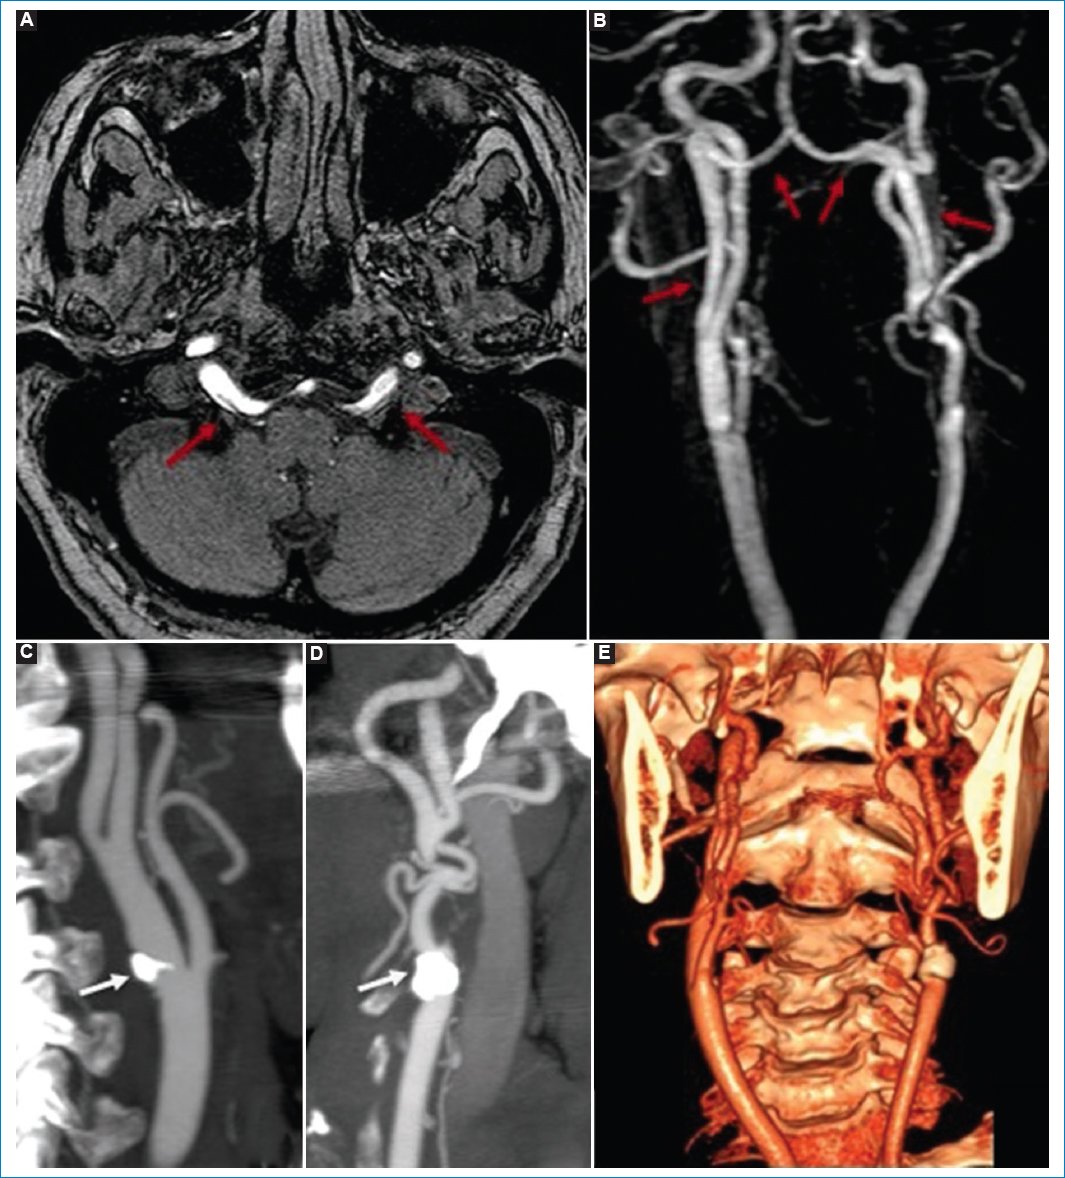

En las secuencias ARM 3D TOF en el plano axial y reconstrucción 3D MIP de vasos cervicales e intracraneales, y en la angiografía por TC con reconstrucción MIP y 3D de los vasos cervicales, se observaron AHP bilaterales emergiendo en el tercio medio del segmento cervical de las ACI (tipo 1) e ingresando en la fosa posterior a través del canal hipogloso, conformando el TB. Se asoció a agenesia de ambas AV y presencia de ateromatosis en ambas bifurcaciones carotídeas, por placas parietales mixtas predominantemente cálcicas (con mayor afectación del izquierdo, determinando una estenosis luminal significativa > 70%). Estos hallazgos condicionaban un mayor riesgo de evento vascular isquémico o embólico en los territorios cerebrales posteriores (Fig. 5).

Figura 5. Secuencia de ARM 3D TOF en el plano axial (A) y reconstrucción 3D MIP de vasos cervicales e intracraneales (B), angiografía por TC con reconstrucción MIP de los vasos cervicales derecho (C) e izquierdo (D), y angiografía por TC con reconstrucción 3D de los vasos cervicales (E). Se observan las arterias hipoglosas bilaterales (flechas rojas) emergiendo en el tercio medio del segmento cervical de la ACI (tipo 1) e ingresando en la fosa posterior a través del canal hipogloso, formando el TB y dando origen a la circulación posterior. Se nota agenesia de las AV bilaterales. Destaca la ateromatosis de los sistemas carotídeos cervicales bilaterales (flechas blancas).